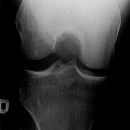

Kniegelenk a.p.

Frakturen im Bereich des Kniegelenks meist durch starke Gewalteinwirkung -> nach zusätzlichen Verletzungen fanden.

CAVE: CT-Indikation: bei V.a. Femurkondylenfraktur/Tibiakopffraktur

MRT-Indikation: zur Darstellung nichtossärer Gelenkanteile oder OD

Beurteilungskriterien

• Physiologisch leichte Valgusstellung von 7-9°. Mechanische Beinachse nach Miculicz (Traglinie Femurkopfzentrum – Mitte OSG) steht normalerweise senkrecht auf der Tangente an die Femurkondylen (Transversalebene des Kniegelenks)

• Weite des femorotibialen Gelenkspaltes beträgt 3-5 mm. Der Laterale erscheint aufgrund etwas kräftigerer Knorpelschicht etwas weiter.

• Weichteilkonturen, Kollateralbänder, Patella- und Quadrizepssehnenruptur: Unschärfe der jeweiligen Kontur.

• Target areas: Eminentia intercondylaris, Tibiaplateaukanten, Fibulaköpfchen

• Posttraumatische periartikuläre Verkalkungen (Stieda-Pellegrini-Schatten): z.B. Ausriß am Ansatz des M. adductor magnus, Kollateralbandossifikation, Kollateralbandausriß mit muldenartigem Defekt am Kondylus

• Normvarianten z.B: am häufigsten Patella partita (meist kraniolateral), akzessorische Knochenkerne (häufig im lateralen oberen Quadranten und häufig bilateral, rund mit zirkulärer Kortikalis), Fabella, persistierende Tibiaapophyse, Sulcus popliteus (Delle am Epikondylus lat.), Tuberculum adductorium (oberhalb Epikondylus med.)